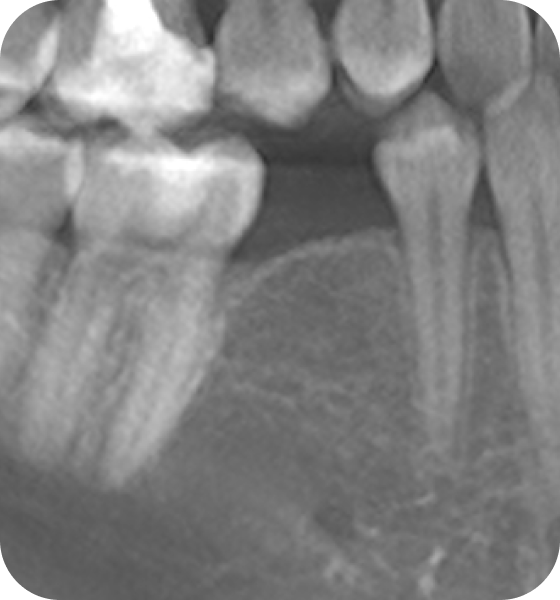

Для чего делают костную пластику?

Часто бывает, что после удаления зуба кость атрофируется, и нет условий для установки импланта. Требуется костная пластика - наращивание костной ткани с использованием искусственного костного материала